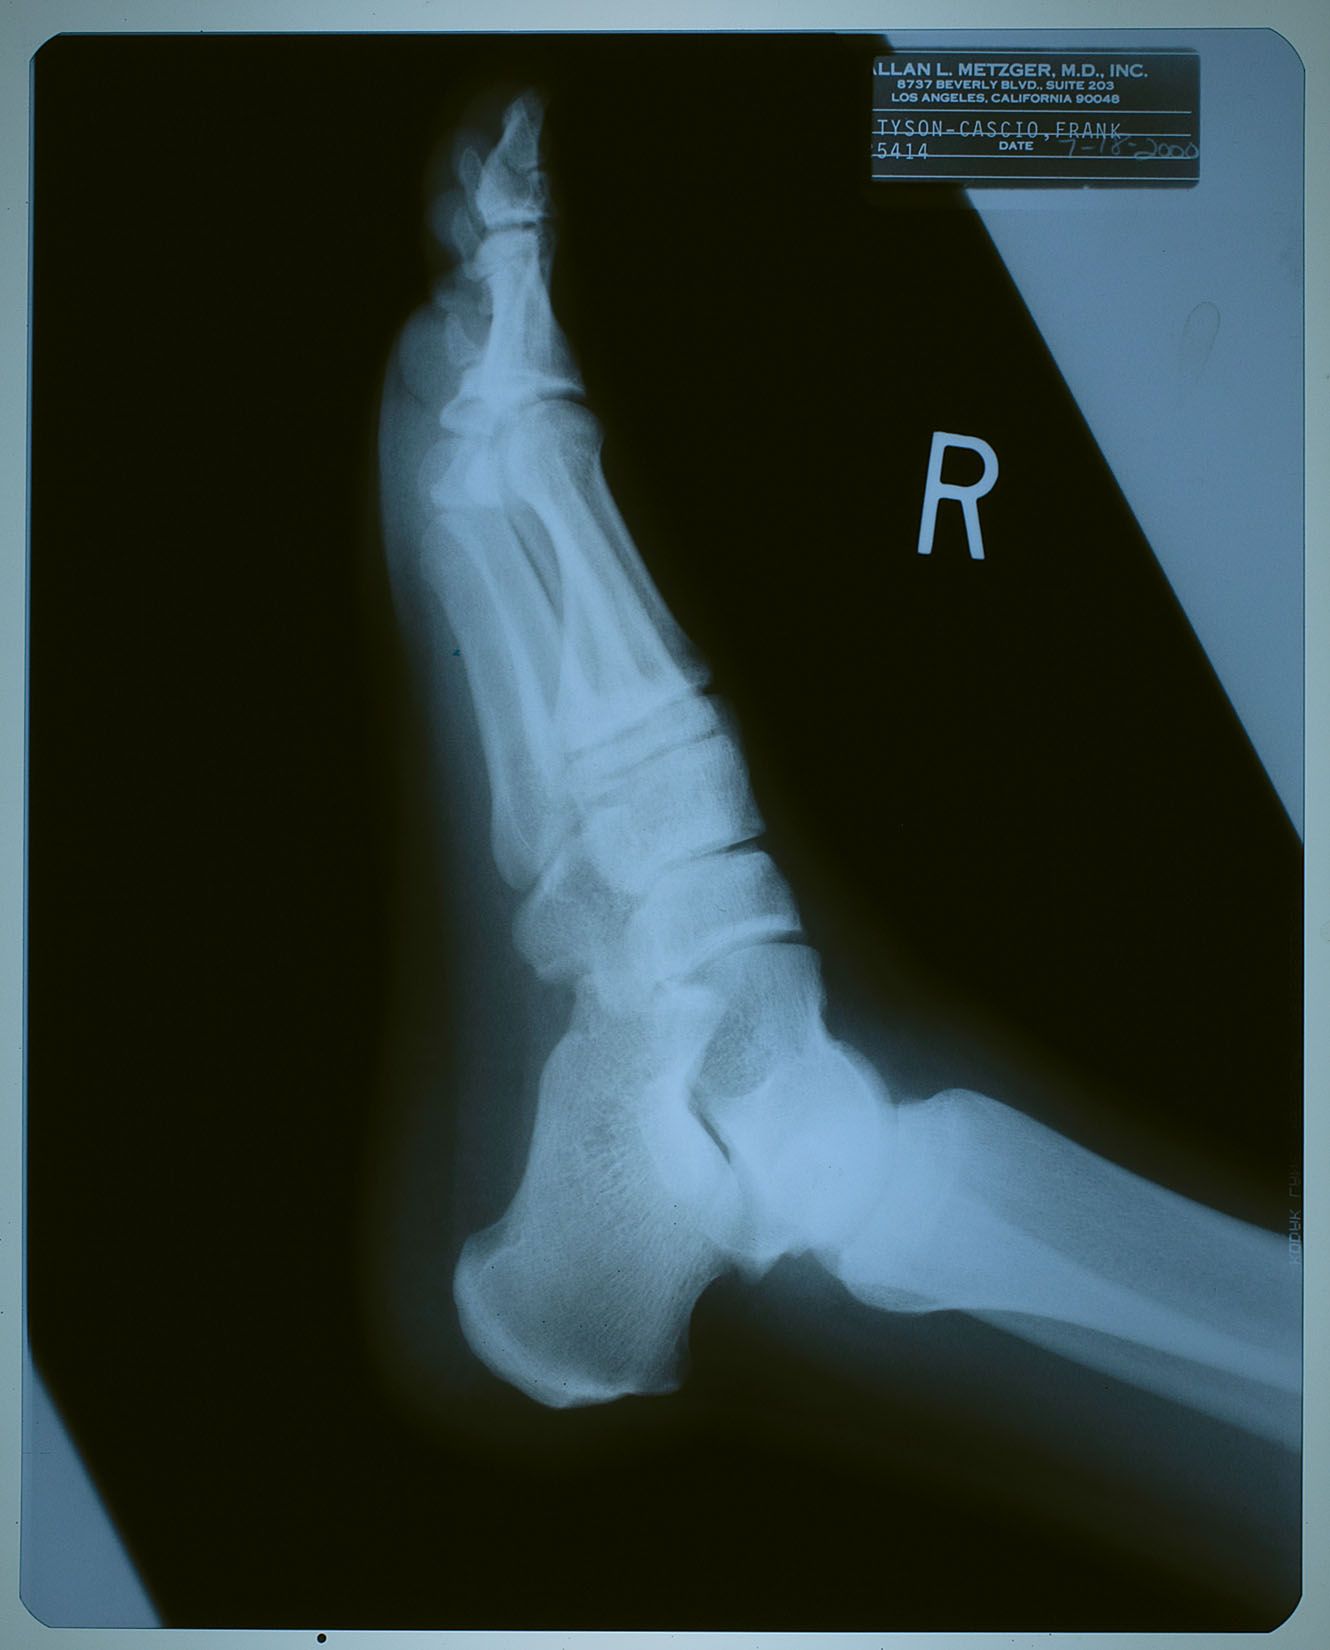

2000年7月18日、ネバーランドで子供たちと遊んでいて

怪我をした時に撮ったX線写真。

名前が 「タイソン-カシオ,フランク」 になっているけども、

カシオ本を読んだ御仁はお判りでしょう。

"タイソン" というのは、前年からマイケルの代理人を務めるようになった

フランク・カシオ君の仕事上での通名。

診療所などでは、マイケルがプライバシー面からフランク君の名を使う事もあったそう。